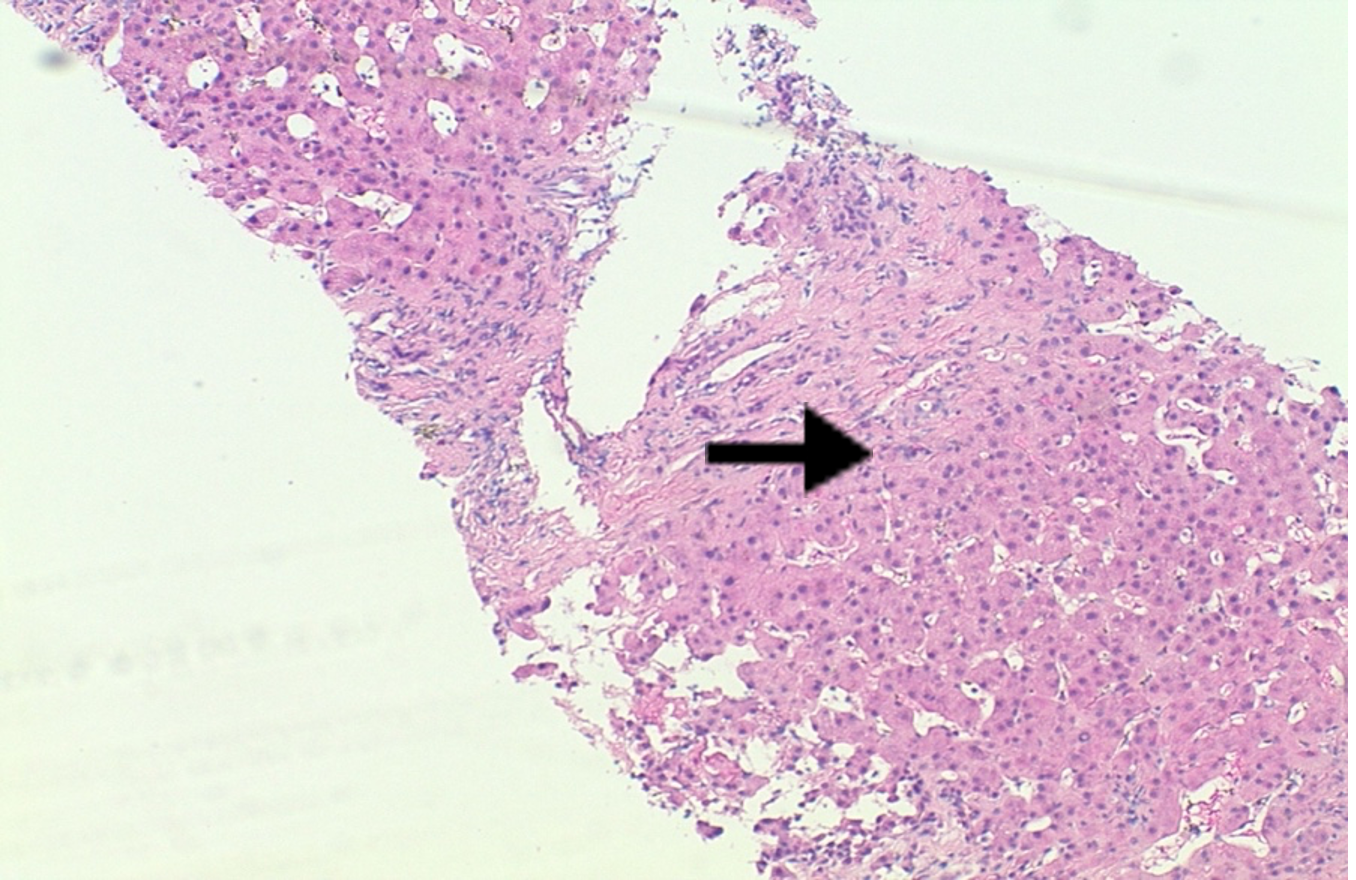

Thorough imaging and serologic workup for the new onset cirrhosis was negative including a viral hepatitis panel and iron studies. A right heart catheterization revealed sinus venosus ASD with a left to right shunt at the superior vena cava and the right atrium junction. A liver biopsy revealed pericellular fibrosis and sinusoidal dilation confirming cardiac cirrhosis (Images 3 and 4)

Image 4. Liver biopsy: Trichrome stain highlights sinusoidal dilation, periportal and focal bridging, and focal pericellular fibrosis.

Diagnoses: Cardiac cirrhosis and ascites due to right heart failure from an underlying ASD was diagnosed. Cirrhosis and ascites from cardiac causes is uncommon1, but the key clue to the cause of this patient’s ascites was the elevated peritoneal fluid protein. About 95% of patients with peritoneal fluid protein > 2.5 g/dL are related to cardiac conditions. This finding led to the workup and eventual diagnosis of the patient’s underlying ASD. An ASD is the second most common cardiac congenital abnormality and can be reliably detected with a bubble study3. A liver biopsy, the gold standard diagnostic test, confirmed cardiac cirrhosis with fibrosis of hepatic veins and sinusoids.